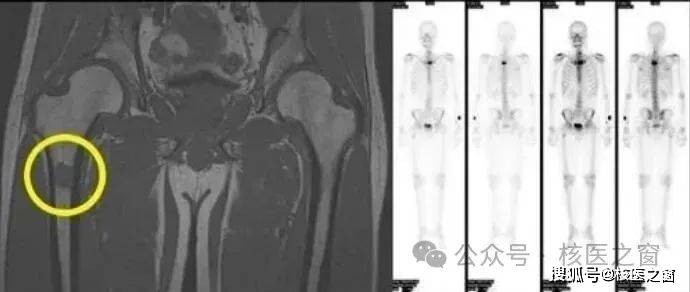

03病理性骨折,被肿瘤侵蚀的骨组织硬度降低,轻微外伤甚至无任何诱因